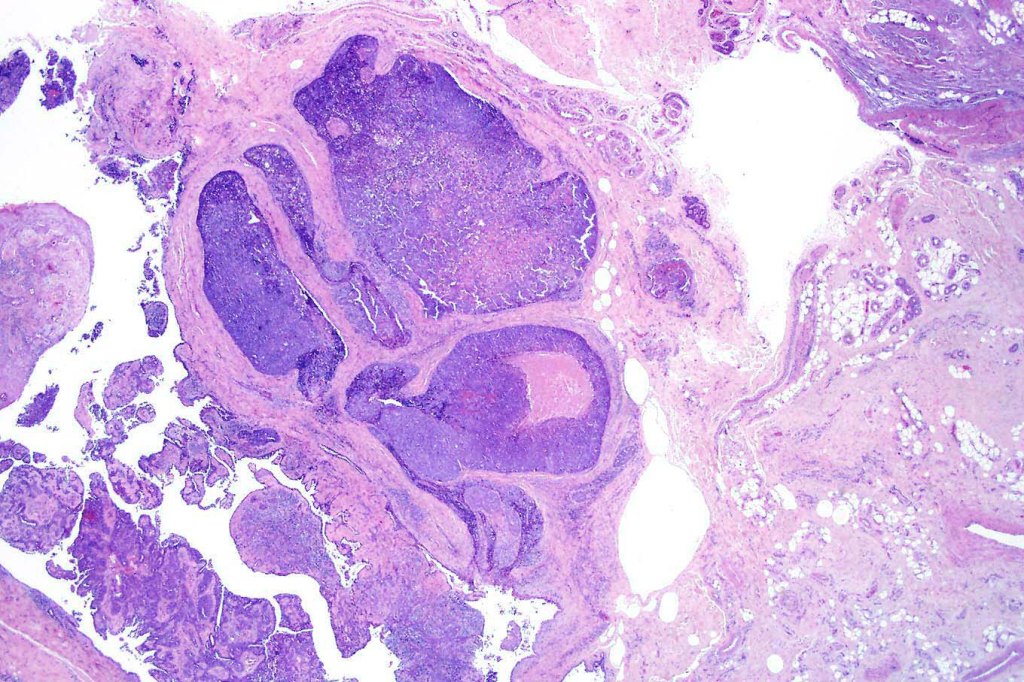

Histological features

•Frequently circumscribed solid/cystic dermal nodule, infiltrative margin rare

•Papillary component (may include pseuopapillae & true papillae with a fibrovascular core)

•Back-to-back glands with double-layered epithelium

•Often dense, hyalinized collagenous stroma

In the majority of cases, digital papillary adenocarcinoma is easily recognised even at scanning magnification. Very exceptionally, a metastasis from a visceral papillary carcinoma must be excluded. Clinicopathological correlation should resolve the matter. Where doubt remains, identification of a myoepithelial layer and CK7 expression will confirm the diagnosis. Some cases can appear deceptively bland and papillary eccrine adenoma may have to be excluded. Again clinicopathological correlation is valuable as is the identification of true papillae, nuclear pleommorpism and excessive mitotic activity.